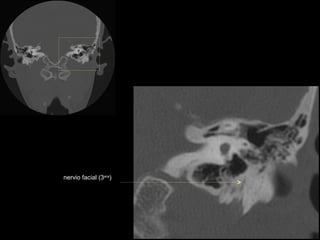

CATEDRA DE RADIOLOGIA U.N.L.P.   Hueso temporal normal        Edición 2002

nervio facial (3era)